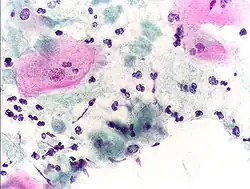

- Micrograph of a normal pap smear

- Micrograph of a Pap test showing a low-grade intraepithelial lesion (LSIL) and benign endocervical mucosa. Pap stain.

- Micrograph of a Pap test showing trichomoniasis. Trichomonas organism seen in the upper right. Pap stain.

-

- Endocervical adenocarcinoma on a pap test.

- Candida organisms on a pap test.

- Viral cytopathic effect consistent with herpes simplex virus on a pap test.

- Normal squamous epithelial cells in premenopausal women

- Atrophic squamous cells in postmenopausal women

- Normal endocervical cells should be present into the slide, as a proof of a good quality sampling

- The cytoplasms of squamous epithelial cells melted out; many Döderlein bacilli can be seen.

- Infestation by Trichomonas vaginalis

- An obviously atypical cell can be seen